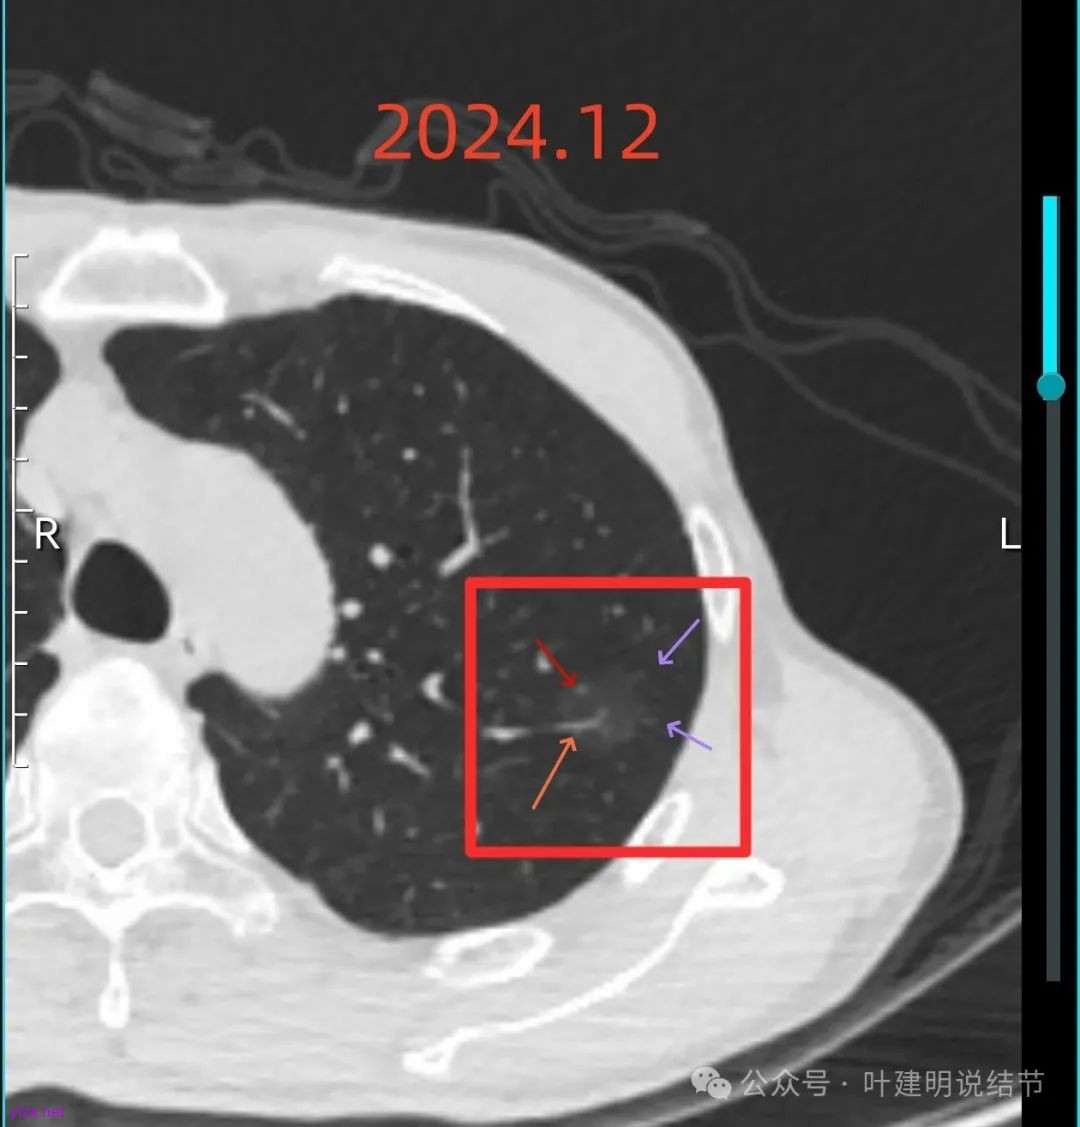

左上病灶血管进入了病灶且有异常增粗,边缘有淡的细毛刺的样子。

灶内血管明显,管壁略毛糙,有异常增粗,红色箭头处有点状高密度,边缘有毛刺征。

灶内出现了明显的实性成分,整体轮廓较清。

除了原血管进入外,另外角度也见到其他血管发出分支走向病灶,而且灶内密度不均,实性成分明显。

绿色的像是慢性炎,随访没有进展;红色的2022年12月开始是纯磨玻璃密度,但有小血管进入和整体轮廓较清,这种密度风险不高,但随访持续在的话,则要考虑肿瘤范畴,不典型增生或原位癌可能性大。再看2025年12月的,范围有所增大,磨玻璃部分密度仍很淡,但灶内出现实性成分,实性成分不太密实,稍显模糊。我觉得像微浸润性腺癌或原位癌伴肺泡塌陷可能性大。位置还好,病灶也不太小,若再增大进展切除范围更多些,我倾向单孔胸腔镜下局部楔形切了为妥。意见供参考!